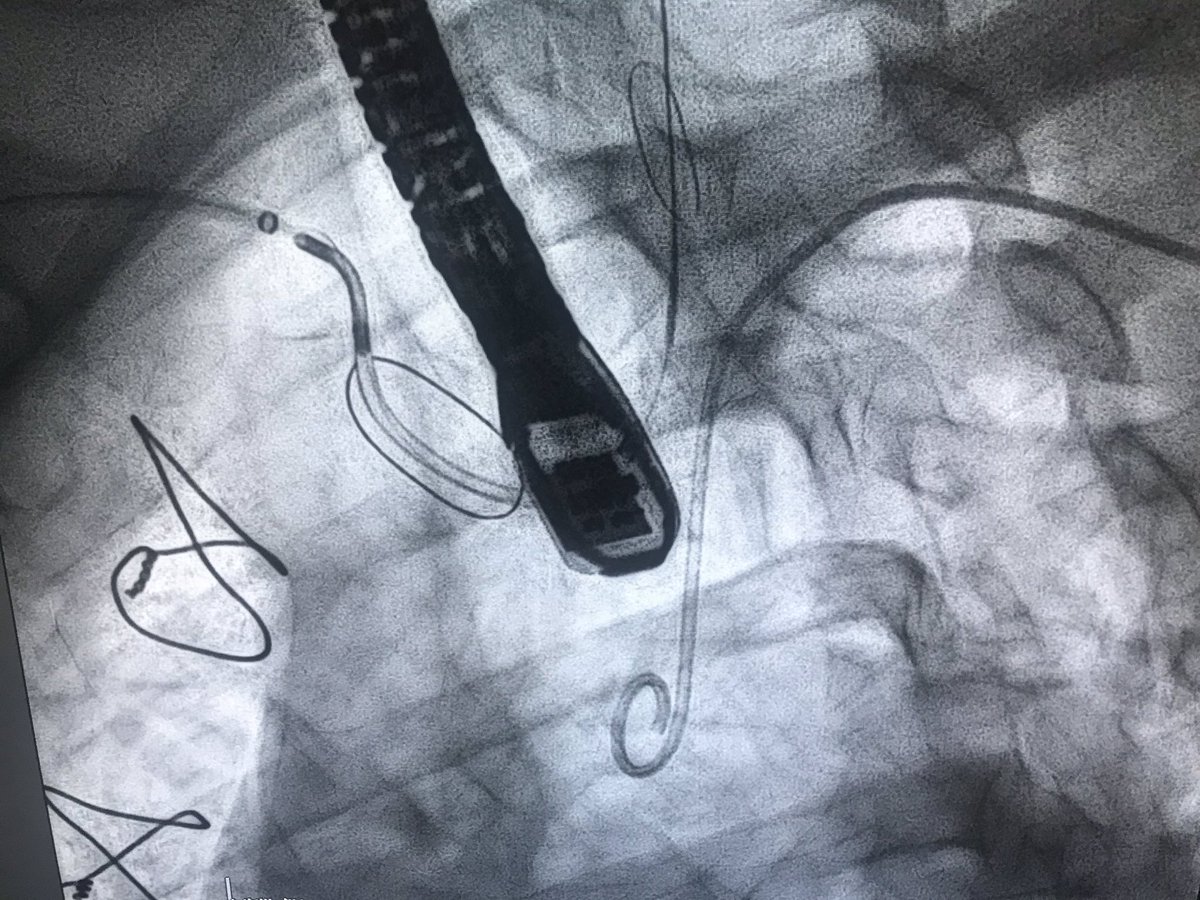

You have to see to believe

#TriClip is a new hope